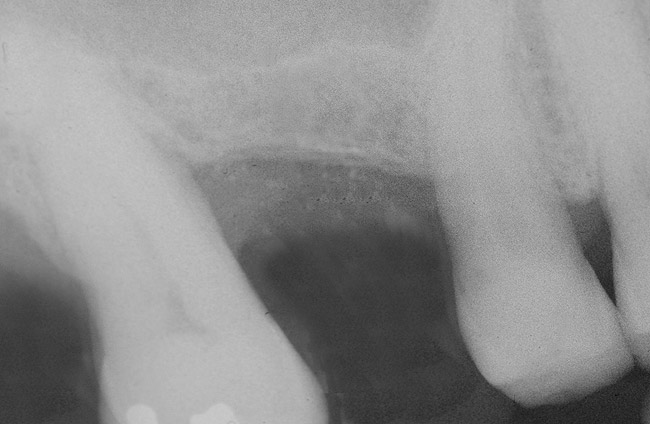

Recently, Jung et al20 indicated the total mean reduction in the grafted bone height was 1.9 mm 5 years after a transcrestal sinus floor elevation. It is not uncommon to detect that bone remodeling occurs over time (Figure 6 and Figure 7). In particular, bone that initially appears apical to the inserted implant resorbs and, subsequently, the osseous crest is found at the apex of the implant.

Figure 6  At site No. 14, a radiograph depicting the full "dome" of graft material apical to the implant.

Figure 6

Figure 7  Radiograph depicting a "flattening" of the dome that has taken place in the first year after the graft was performed. This shows consolidation of the graft and remodeling that takes place over time.

Figure 7